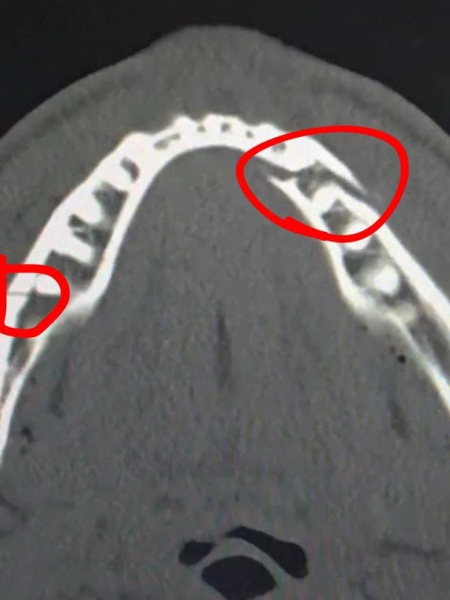

Пол вирушив до лікарні, де зробив рентгенівський знімок, який показав, що у нього зламана щелепа у двох місцях.

“Перелом щелепи в двох місцях. Дайте мені Канело через 10 днів”, – написав Пол.